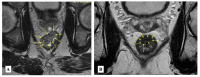

The administration of neoadjuvant chemoradiotherapy (nCRT) followed by total mesorrectal excision (TME) and selective use of adjuvant chemotherapy can still be considered the standard of care in locally advanced rectal cancer (LARC). However, avoiding sequelae of TME and entering a narrow follow-up program of watch and wait (W&W), in select cases that achieve a comparable clinical complete response (cCR) to nCRT, is now very attractive to both patients and clinicians. Many advances based on well-designed studies and long-term data coming from big multicenter cohorts have drawn some important conclusions and warnings regarding this strategy. In order to safely implement W&W, it is important consider proper selection of cases, best treatment options, surveillance strategy and the attitudes towards near complete responses or even tumor regrowth. The present review offers a comprehensive overview of W&W strategy from its origins to the most current literature, from a practical point of view focused on daily clinical practice, without losing sight of the most important future prospects in this area.